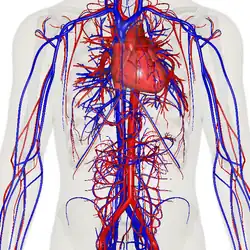

![]() The human circulatory system (simplified). Red indicates oxygenated blood carried in arteries. Blue indicates deoxygenated blood carried in veins. Capillaries join the arteries and veins. | |

In vertebrates, the circulatory system is a system of organs that includes the heart, blood vessels, and blood which is circulated throughout the body.[1][2] It includes the cardiovascular system, or vascular system, that consists of the heart and blood vessels (from Greek kardia meaning heart, and Latin vascula meaning vessels). The circulatory system has two divisions, a systemic circulation or circuit, and a pulmonary circulation or circuit.[3] Some sources use the terms cardiovascular system and vascular system interchangeably with circulatory system.[4]

The network of blood vessels are the great vessels of the heart including large elastic arteries, and large veins; other arteries, smaller arterioles, capillaries that join with venules (small veins), and other veins. The circulatory system is closed in vertebrates, which means that the blood never leaves the network of blood vessels. Many invertebrates such as arthropods have an open circulatory system with a heart that pumps a hemolymph which returns via the body cavity rather than via blood vessels. Diploblasts such as sponges and comb jellies lack a circulatory system.

Structure

The circulatory system includes the heart, blood vessels, and blood.[2] The cardiovascular system in all vertebrates, consists of the heart and blood vessels. The circulatory system is further divided into two major circuits – a pulmonary circulation, and a systemic circulation.[8][1][3] The pulmonary circulation is a circuit loop from the right heart taking deoxygenated blood to the lungs where it is oxygenated and returned to the left heart. The systemic circulation is a circuit loop that delivers oxygenated blood from the left heart to the rest of the body, and returns deoxygenated blood back to the right heart via large veins known as the venae cavae. The systemic circulation can also be defined as two parts – a macrocirculation and a microcirculation. An average adult contains five to six quarts (roughly 4.7 to 5.7 liters) of blood, accounting for approximately 7% of their total body weight.[9] Blood consists of plasma, red blood cells, white blood cells, and platelets. The digestive system also works with the circulatory system to provide the nutrients the system needs to keep the heart pumping.[10]